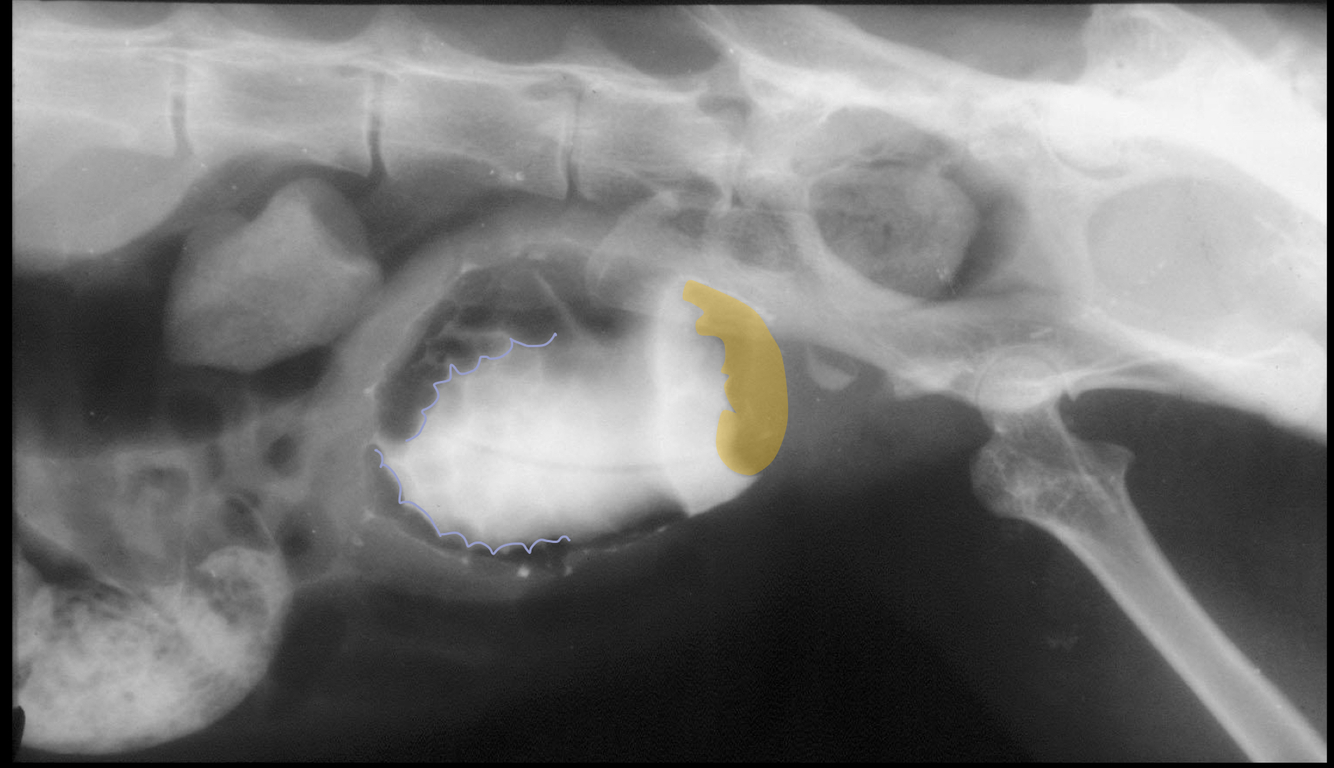

Q

What is likely causing the observed filling defect?

• filling defect at trigone, common spot for TCC

• wall thickening

What is a contrast filling defect? What does it indicate? What does it allow?

A

absence of contrast from an area where contrast would normally be expected

presence of something abnormal occupying the space

aids in identification of luminal and mural lesions